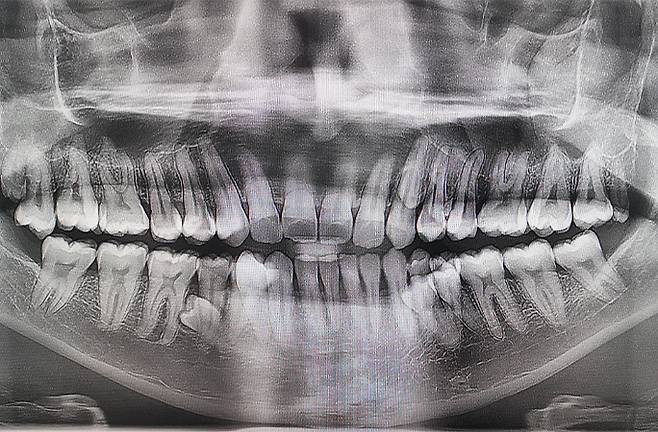

11일 기네스 세계기록에 따르면, 말레이시아 남성 프라탑 무니안디(33)는 최근 ‘최다 치아 보유 남성’ 부문에 이름을 올렸다. 그의 치아 개수는 총 42개로, 일반 성인 치아 개수(32개)보다 10개 더 많다.

앞서 프라탑은 두 명의 치과의사의 검진을 통해 치아 개수를 확인했다. 검사 결과, 그는 42개 치아 외에도 잇몸 속에 매복한 치아가 2개 더 있는 것으로 나타났다.

프라탑은 42개 치아가 모두 정상적으로 자랐으며, 건강에 별다른 문제가 없는 것으로 전해졌다. 그는 “하루에 두 번 양치질을 하고 정기적으로 치실을 사용하는 등 구강 위생을 철저히 관리하기 위해 노력하고 있다”며 “치아는 나에게 어떤 영향도 미치지 않는다”고 말했다. 이어 “내가 알려주기 전까지 대부분 사람들이 나의 덧니를 알아차리지 못한다”며 “비밀리에 세계 기록을 보유한 사람이 얼마나 될지 궁금하다”고 했다.